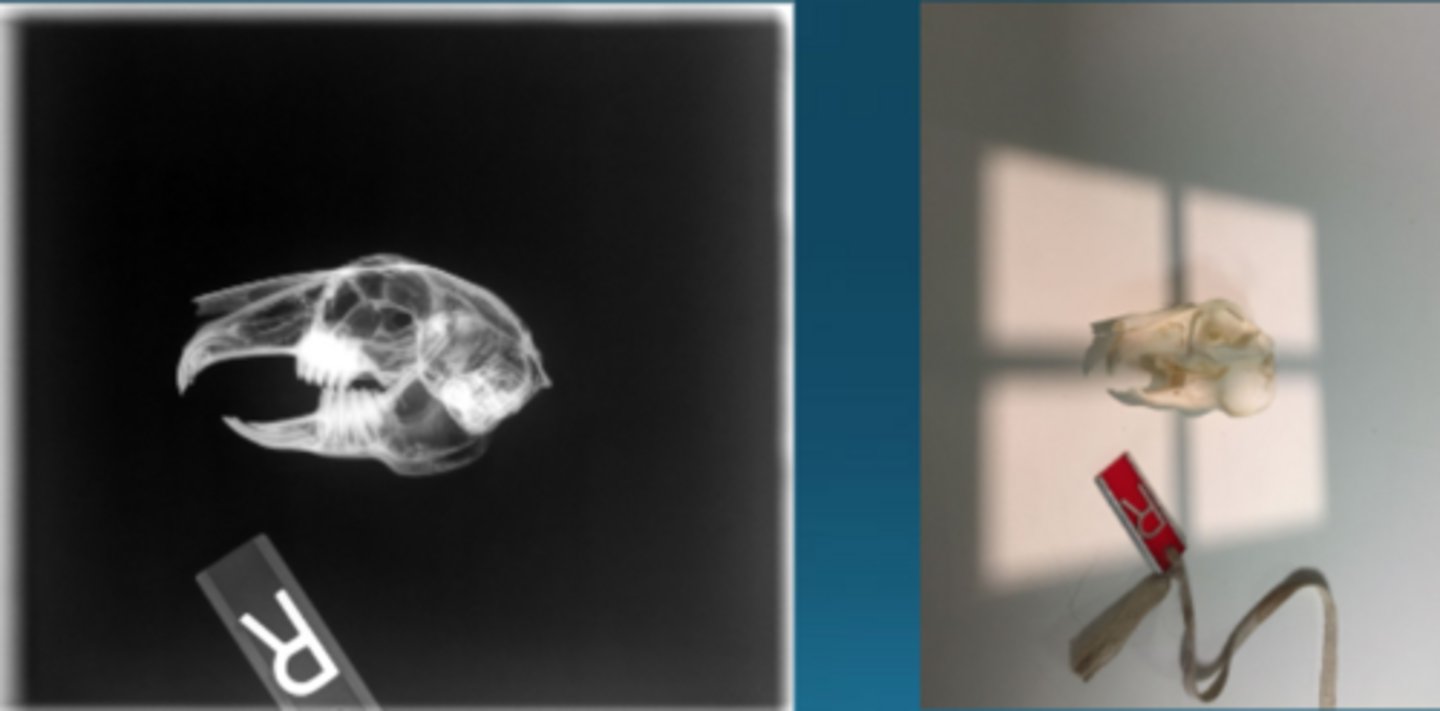

Oblique

What radiographic view it this to image rabbits?

To see individual bullae and see dental pathology

Why would you take oblique radiographs in rabbits?

CT

What type of imaging is this in rabbits to see dental disease?